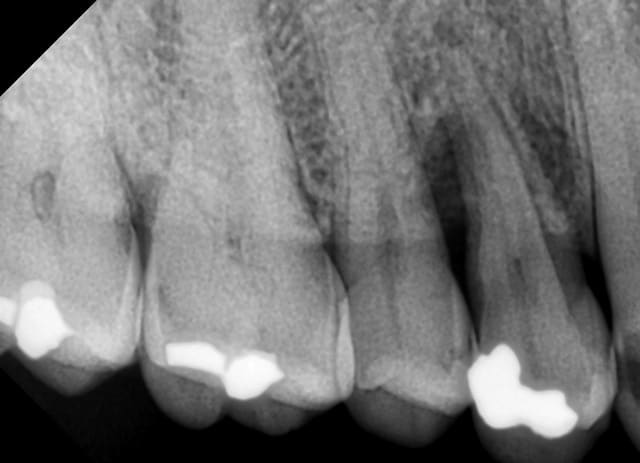

Aujourd'hui, il va perdre sa 14 avec une jolie perte osseuse. Le reste de la bouche est ok, pas de problème ni d'hygiène ni d'occlusion, 15 et 13 sont saines (sauf une carie en distal de 13).

Tu as des pertes osseuses importantes ? ou juste angulaire avec maintient de la corticale vestibulaire et palatine ?

Après, pour ce qui est de la ROG, je la fais justement parce qu'on a perdu la corticale palatine, histoire d'être certain de ne pas perdre + d'os.

Au bout de 6 mois post-radiothérapie on sait que le tissu osseux est hypoxique, hypovasculaire et hypocellulaire (triade de Marx). Ce n'est que mon avis, mais je pense que la carie de la 14 a constitué une porte d'entrée à l'infection de l'os alvéolaire sous-jacent. Donc de toute façon, je pense qu'il y a déjà un phénomène d'ORN.